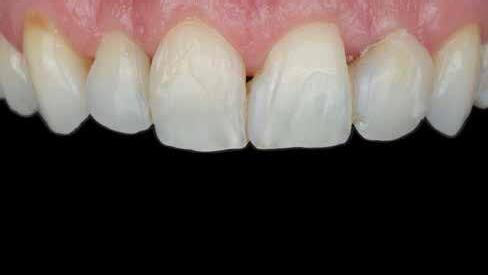

Egy 30 éves, negatív kórtörténettel rendelkező beteg azzal a kéréssel fordult hozzánk, hogy cseréljük ki az UR1 traumája után, 10 évvel korábban készült korábbi kompozit-helyreállítást.

A klinikai vizsgálat során az UR1 reagál a viabilitási tesztre, és az ugyanazon a napon készült röntgenfelvételen nem mutat periapikális elváltozásokat (1. ábra).

Az UR1 elszíneződött, és palatálisabb helyzetben van, mint az ellenoldali központi UL1 (2. ábra)

Az esztétikai elemzés a gingivális zenit aszimmetriáját mutatja az UR1 és az UL1 között. Parodontális szonda segítségével, plexusérzéstelenítés után, az IA

típusú funkcionális hám megváltozott passzív erupcióját igazoljuk Coslet és mtsai. osztályozása szerint (3. ábra)

A lehető legkonzervatívabb helyreállító kezelés elvégzése érdekében a páciensnél, figyelembe véve a megtartott fogelem korát és vitalitását, a tervezés és a diagnosztikai felviaszolás után a közvetlen kompozit-helyreállítás elvégzése mellett döntünk.

A kezelés napján, helyi plexusérzéstelenítést követően, az UR1-et kofferdámmal izoláljuk, kiterjesztve az izolációt az első premolárisokra (4. ábra)

Ezt követően eltávolítjuk a törött kompozt-helyreállítást, és az előkészített fogon rövid ferdére preparálást készítünk, majd az UR1 teljes felületén homokfúvást végzünk 27 μm-es alumínium-oxid porral (5. ábra)

A megváltozott passzív erupció korrigálása érdekében úgy döntöttünk, hogy a fog kiemelkedési profilját a vesztibuláris kidomborodás hangsúlyozásával és az ellenoldali elemmel való szimmetriára törekvéssel újra létrehozzuk. Erre a célra

egy előre megformázott fémmatricát használunk, amelyet két ékkel blokkolunk.

A matrica adaptálása után az adhéziós eljárásokat egy 3 lépéses etch&rinse rendszerrel végezzük. Minden egyes lépést 40 másodperces, UV-fénnyel történő polimerizálás követ (6. ábra)

A vesztibuláris kiemelkedési profilt zománcszínű kompozittal (a TOKUYAMA DENTAL ESTELITE ASTERIA WE termékével) állítjuk helyre (7. ábra).

A diagnosztikai felviaszolás szilikonindexének elkészítése után a palatinális falat zománcszínű kompozittal (a TOKUYAMA DENTAL ESTELITE ASTERIA WE termékével) helyreállítjuk (8. ábra)

Ezt követően helyreállítjuk a dentin anatómiáját a mamelonok reprodukálásával egy átlátszatlan dentinszínű kompozittal (a TOKUYAMA DENTAL ESTELITE SIGMA QUICK OA2 termékével); ez a szín alapvető fontosságú lesz a diszkromatikus elem színének korrigálásához is (9. ábra) Világoskék és fehér hatású árnyalatokat (a TOKUYAMA

DENTAL ESTELITE COLOR termékét) alkalmazunk az opá-

losság emulálásához az incizális területen (10. ábra)

A rétegezést egy zománcszín (a TOKUYAMA DENTAL ESTELITE ASTERIA WE terméke) használatával végezzük a vesztibulárisban, egyszeri hozzáadással. A vesztibuláris felületet háromdimenziós térfogatban modellezzük és vezéreljük annak érdekében, hogy a lehető legkevesebb végső kiigazítás legyen. Ezután 20 másodpercig polimerizáljuk, majd 40 másodpercig polimerizáljuk vesztibulárisan és palatinálisan, miután bevontuk őket gliceringéllel a kompozit hibrid rétegének elkerülése érdekében (11. ábra).

A finírozási és polírozási eljárásokat úgy végezzük, hogy megpróbáljuk emulálni az UL1 átmenő vonalait (12–13. ábra)

A pácienst 21 nap (14–15. ábrák) és 12 hónap (16. ábra) után ismét ellenőrizzük, hogy értékeljük az esztétikai eredményt a forma és a szín tekintetében.